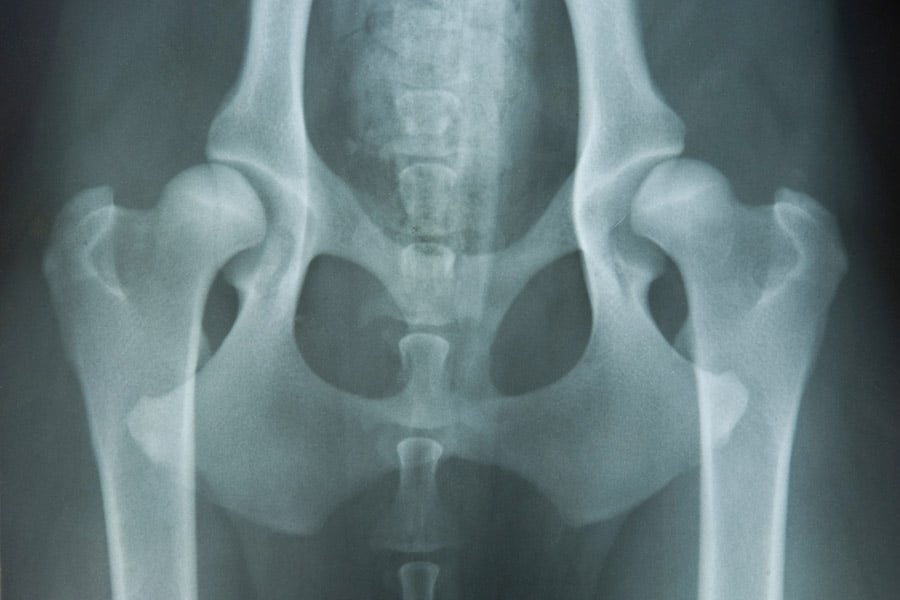

Тазобедрена

Има деца с проявено състояние, наречено дисплазия на тазобедрената става или такава на развитието на въпросната става (Developmental Dysplasia of the Hip, DDH).

Това може да означава, че:

- Въпросната става е с неправилна форма.

- Тазобедрената ямка не е на правилното място, за да покрие и поддържа костта на крака.

Резултатът от това е повече износване и разкъсване на всяка част от тазобедрената става.